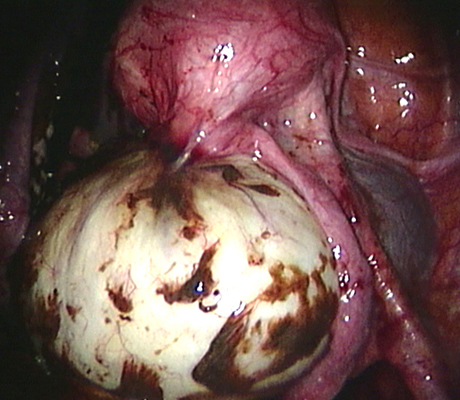

Endometriosis is a non-cancerous condition where the endometrial tissue or womb lining which normally grows only in the uterus is found in other parts of your pelvis, for example the ovaries, fallopian tubes, rectum, bladder, appendix and pelvic walls. This womb lining that grows outside the uterus responds also to hormones but at the time of your periods it can not be expelled (as the womb lining) and causes pain, cysts in the ovaries (called chocolate cysts), inflammation in your pelvis, scar tissue, pain with sexual intercourse, chronic pelvic pain, pain when passing bowel motions, lower backache, symptoms similar to urinary tract infections, premenstrual discomfort, etc.

Laparoscopy is an operation (keyhole surgery) conducted under general anaesthesia. A telescope is introduced into a small incision in your navel, other small incisions are made for using special laparoscopic instruments and all the pelvic organs are examined with magnification (Video-laparoscopy) ; then the endometriosis is treated. Video Laparoscopy allows conservative surgery (hysterectomy is NOT the usual treatment for endometriosis) which means laparoscopic excision of the endometriotic implants, with restoration of the normal anatomy and preservation of the uterus, tubes and ovaries.

There are a number of ways as endometriosis may cause infertility. Although women with mild endometriosis may get pregnant, endometriosis is usually a progressive disease, as it gets worse with time. So early diagnosis and treatment is important. Women with advanced disease have low chance of achieving a spontaneous pregnancy. There is plenty of evidence based medicine showing that laparoscopic treatment of endometriosis does improve fertility. When a patient has an ovarian endometriotic cyst associated with infertility, laparoscopic surgery is the first line of treatment. The average pregnancy rate reported after surgery in these cases is 35-50%. So laparoscopic surgery provides a woman with good chances of becoming pregnant spontaneously.